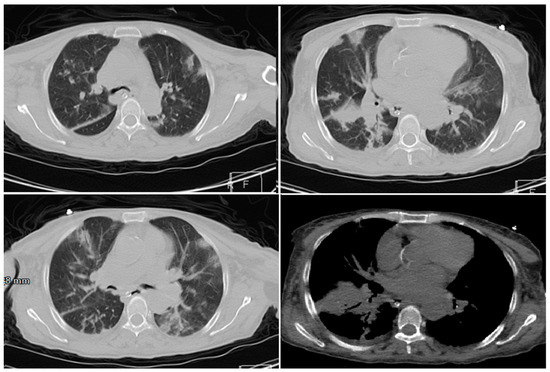

3.1.1. Cases Reports from Iran

Case 1

Case 2

Case 3

Case 4

Case 5

- Mahdavi, A.; Khalili, N.; Davarpanah, A.H.; Faghihi, T.; Mahdavi, A.; Haseli, S.; Sabri, A.; Kahkouee, S.; Kazemi, M.A.; Mehrian, P.; et al. Radiologic Management of COVID-19: Preliminary Experience of the Iranian Society of Radiology COVID-19 Consultant Group (ISRCC). Iran. J. Radiol. 2020. [Google Scholar] [CrossRef]

- Pan, Y.; Guan, H. Imaging changes in patients with 2019-nCov. Eur. Radiol. 2020. [Google Scholar] [CrossRef]

- Ng, M.-Y.; Lee, E.Y.P.; Yang, J.; Yang, F.; Li, X.; Wang, H.; Lui, M.M.-S.; Lo, C.S.-Y.; Leung, B.; Khong, P.-L.; et al. Imaging Profile of the COVID-19 Infection: Radiologic Findings and Literature Review. Radiol. Cardiothorac. Imaging 2020. [Google Scholar] [CrossRef]

- Zu, Z.Y.; Jiang, M.D.; Xu, P.P.; Chen, W.; Ni, Q.Q.; Lu, G.M.; Zhang, L.J. Coronavirus Disease 2019 (COVID-19): A Perspective from China. Radiology 2020. [Google Scholar] [CrossRef]